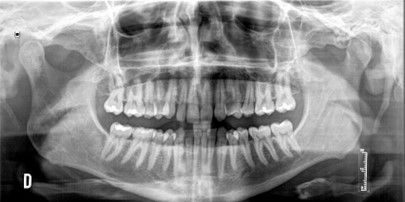

Debido a la agenesia congénita del incisivo lateral superior izquierdo, el paciente fue tratado 12 años atrás mediante ortodoncia convencional para cerrar el diastema (Figuras 1 y 2).

Finalizado el tratamiento con ortodoncia (Figuras 3, 4 y 5), y una vez que el paciente optó por la opción del implante; se repitió el escaneado intraoral y se obtuvo un escáner de haz cónico para la correcta planificación de la cirugía implantológica (Figura 6).